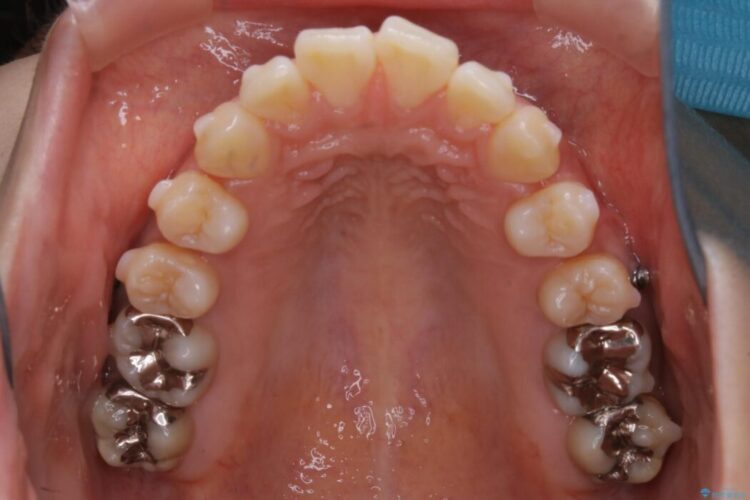

患者様からなおしたい内容をお聞きしたところ

・上下の歯のガタつき

よって患者様ご希望の非抜歯かつマウスピースでの矯正を行うために、最大量の臼歯の遠心移動をして歯列全体を奥へ引っ込める計画をご提案しました。

非抜歯での矯正治療

マウスピースにマイクロインプラントという補助装置を併用することで抜歯をせずとも歯列を整えるスペースを確保することができます。奥歯から順に移動させていくので前歯に変化が出るまでには時間がかかってしまいますが、健康な歯を抜歯することなく理想的な歯並びを手に入れることができます。